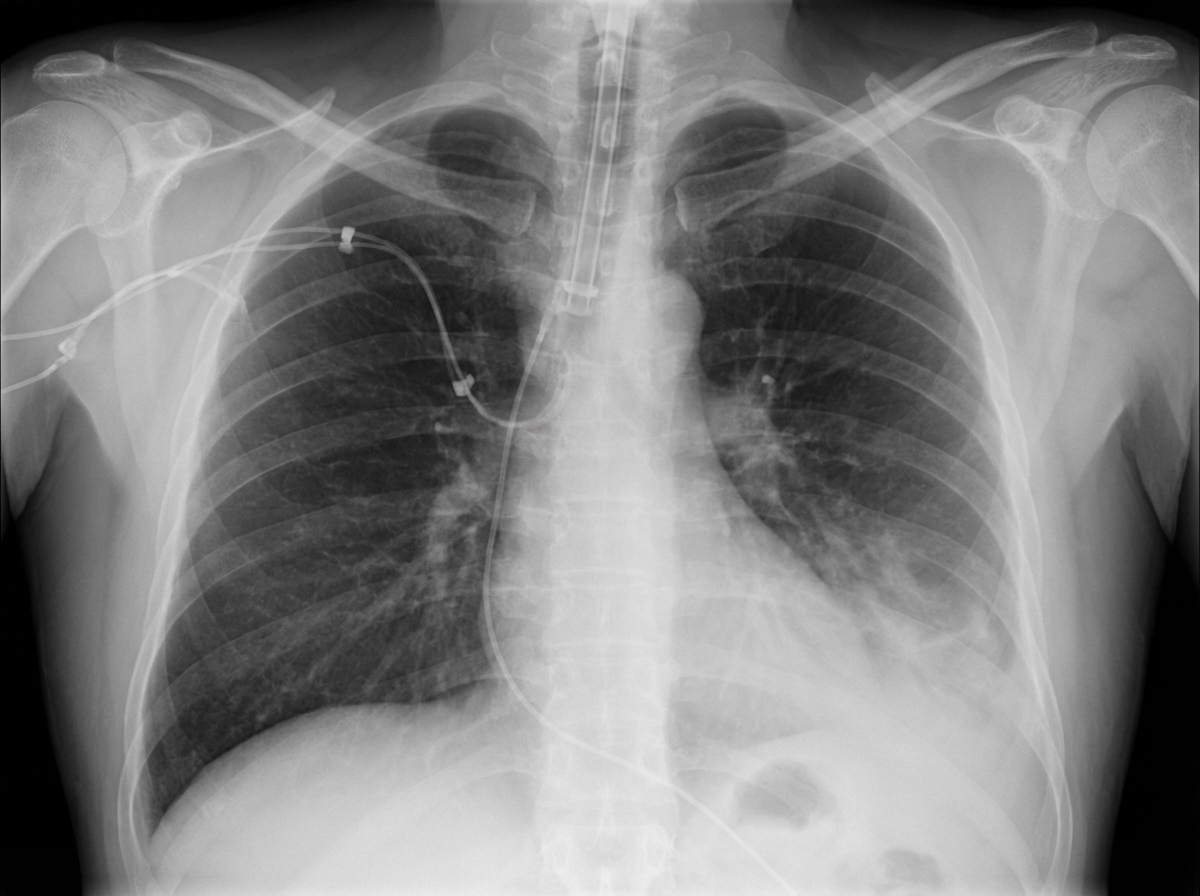

A 27-year-old man is brought to the emergency department 45 minutes after being involved in a motor vehicle collision. He is agitated. He has pain in his upper right arm, which he is cradling in his left arm. His temperature is 36.7°C (98°F), pulse is 135/min, respirations are 25/min, and blood pressure is 145/90 mm Hg. His breathing is shallow. Pulse oximetry on 100% oxygen via a non-rebreather face mask shows an oxygen saturation of 83%. He is confused and oriented only to person. Examination shows multiple bruises on the right anterior thoracic wall. The pupils are equal and reactive to light. On inspiration, his right chest wall demonstrates paradoxical inward movement while his left chest wall is expanding. There is pain to palpation and crepitus over his right anterior ribs. The remainder of the examination shows no abnormalities. An x-ray of the chest is shown. Two large-bore IVs are placed. After fluid resuscitation and analgesia, which of the following is the most appropriate next step in management?